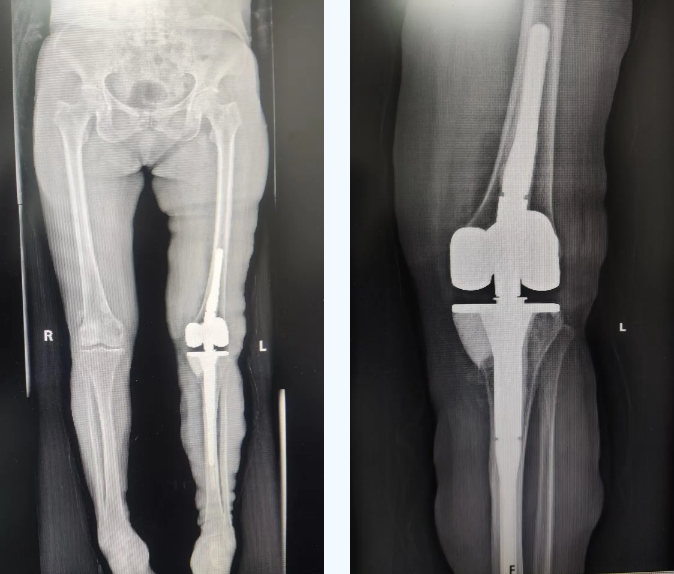

术中,骨关节科医疗团队在手术过程中严格遵循既定方案,凭借精湛的技术和丰富的临床经验,小心翼翼地对患者受损膝关节进行清理、修复并植入了铰链式人工膝关节。手术过程精准高效,历时约 2 小时,成功克服多重技术难关。

术后,在医护团队的精心护理和科学康复指导下,患者恢复良好:膝关节疼痛显著缓解,活动功能稳步恢复。通过定期复查和康复方案调整,其关节功能持续改善,生活质量大幅提升。目前患者康复进程顺利,对治疗效果深感满意。